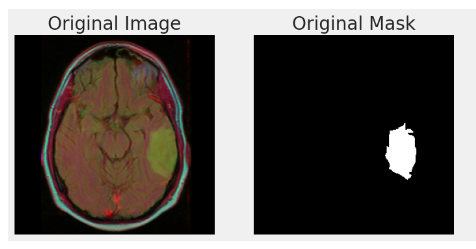

* Brain Tumor Dataset (binary, class 1개)

의료계통에서 많이 사용하는 MRI

https://www.kaggle.com/code/abdallahwagih/brain-tumor-segmentation-unet-dice-coef-89-6

1개인 경우는 색상이 필요없으니까 0과 1로만 표현해요